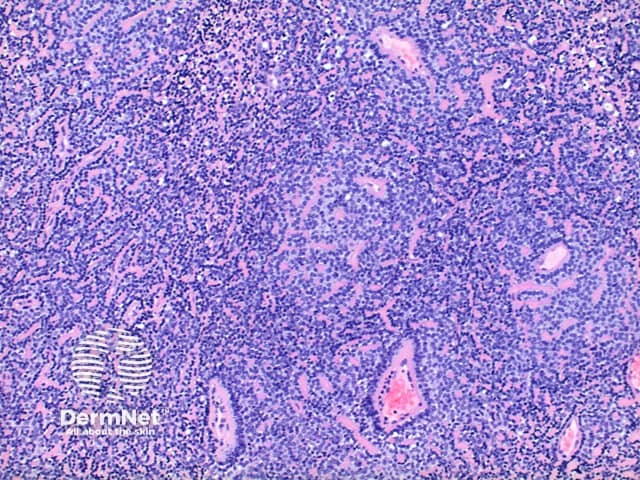

Low power view of eccrine spiradenoma shows a well-circumscribed tumour nodule arising within the dermis or superficial subcutis. The tumour is comprised of a diffuse dense basophilic cellular proliferation (Figures 1 and 2). In some cases a prominent vascular component can be seen (Figures 2 and 3). Eosinophilic hyaline deposits are seen in amongst the tumour cells as droplets and bands (Figure 4). A lymphocytic infiltrate is seen and when heavy can mimic lymphoid tissue.

Figure 2